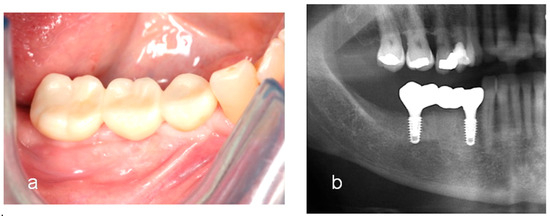

Utilization of Tenting Pole Abutments for the Reconstruction of Severely Resorbed Alveolar Bone: Technical Considerations and Case Series Reports

2. Case Presentations

- Woo, R.H.; Kim, H.G.; Kim, G.; Park, W.E.; Sohn, D.S. Simplified 3-dimensional ridge augmentation using a tenting abutment. Adv. Dent. Oral. Health 2020, 12, 185–205. [Google Scholar]

- Sohn, D.S. Reconstruction of three-dimensional alveolar ridge defects utilizing screws and implant abutments for the tent-pole grafting’ techniques. In Essential Techniques of Alveolar Bone Augmentation in Implant Dentistry, 2nd ed.; Tolstunov, L., Ed.; Wiley Blackwell: Hoboken, NJ, USA, 2023; pp. 404–418. [Google Scholar]